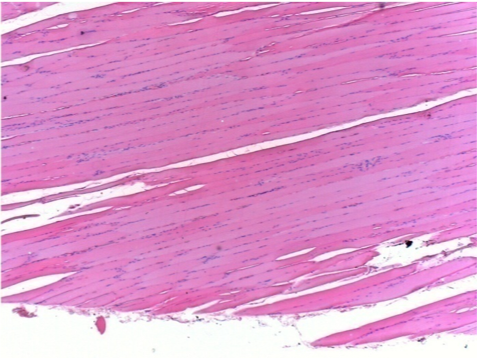

Л: Претибіальний м'яз - без лікування

Через 10 днів після ін'єкції Ендопіл 0,1 мл в правий претибіальний м'яз.